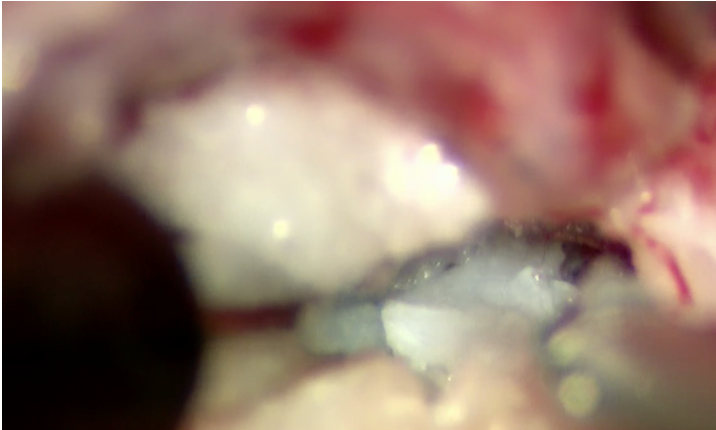

根治治療には逸脱した椎間板物質を摘出する必要があります。胸腰部の椎間板ヘルニアと異なり、頚部では腹側からのアプローチを用います(ベントラルスロット)。まず重要な組織である気管や食道、頸動脈静脈を避け、骨にアプローチします。骨の切削にはラウンドバーとよばれるドリルや、SonoCure(ソノキュア)とよばれる乳化吸引装置を用います。ソノキュアは骨だけを削り、神経や血管などの軟部組織は削れないという利点があります。

今回の症例では骨の幅が9mmであり、削る幅の最大経が3mmでした。それ以上の幅で削ると不安定性が出て合併症のリスクが高くなります。3mmの幅の内部での操作となるため、肉眼での操作は困難であり、顕微鏡操作が有用となります。以下は顕微鏡下での術野の視野になります。

骨をソノキュアによって少しずつ掘っていきます。

穴が深くなっています。

内部の白いものが椎間板物質になります。